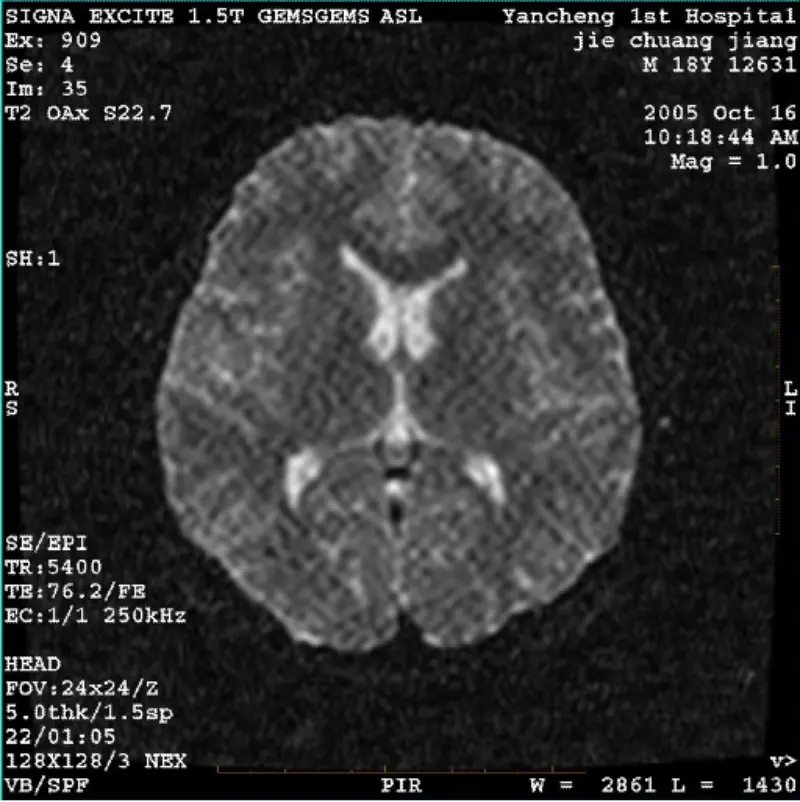

Czytaj więcejSYSTEM: 1,5T Signa Twin Excite II (wersja oprogramowania 11.0M4) PROBLEM/OBJAWY Obraz DWI (tryb powiększenia i tryb cały) i fiesta (tryb powiększenia i tryb cały). widoczny artefakt siatkowy lub sztruksowy, niezależnie od tego, czy używana jest cewka czy głowica cewka, inny typowy obraz wydaj......